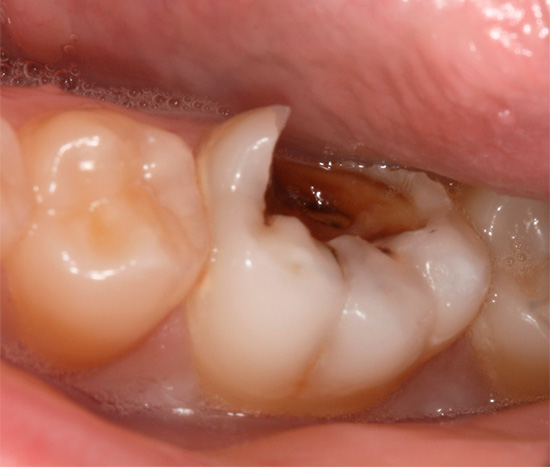

- Perturbações estéticas visíveis aos olhos. Isso se deve ao aumento da área da lesão e à unificação da cárie na base da raiz com defeitos cervicais. A foto a seguir mostra um exemplo: